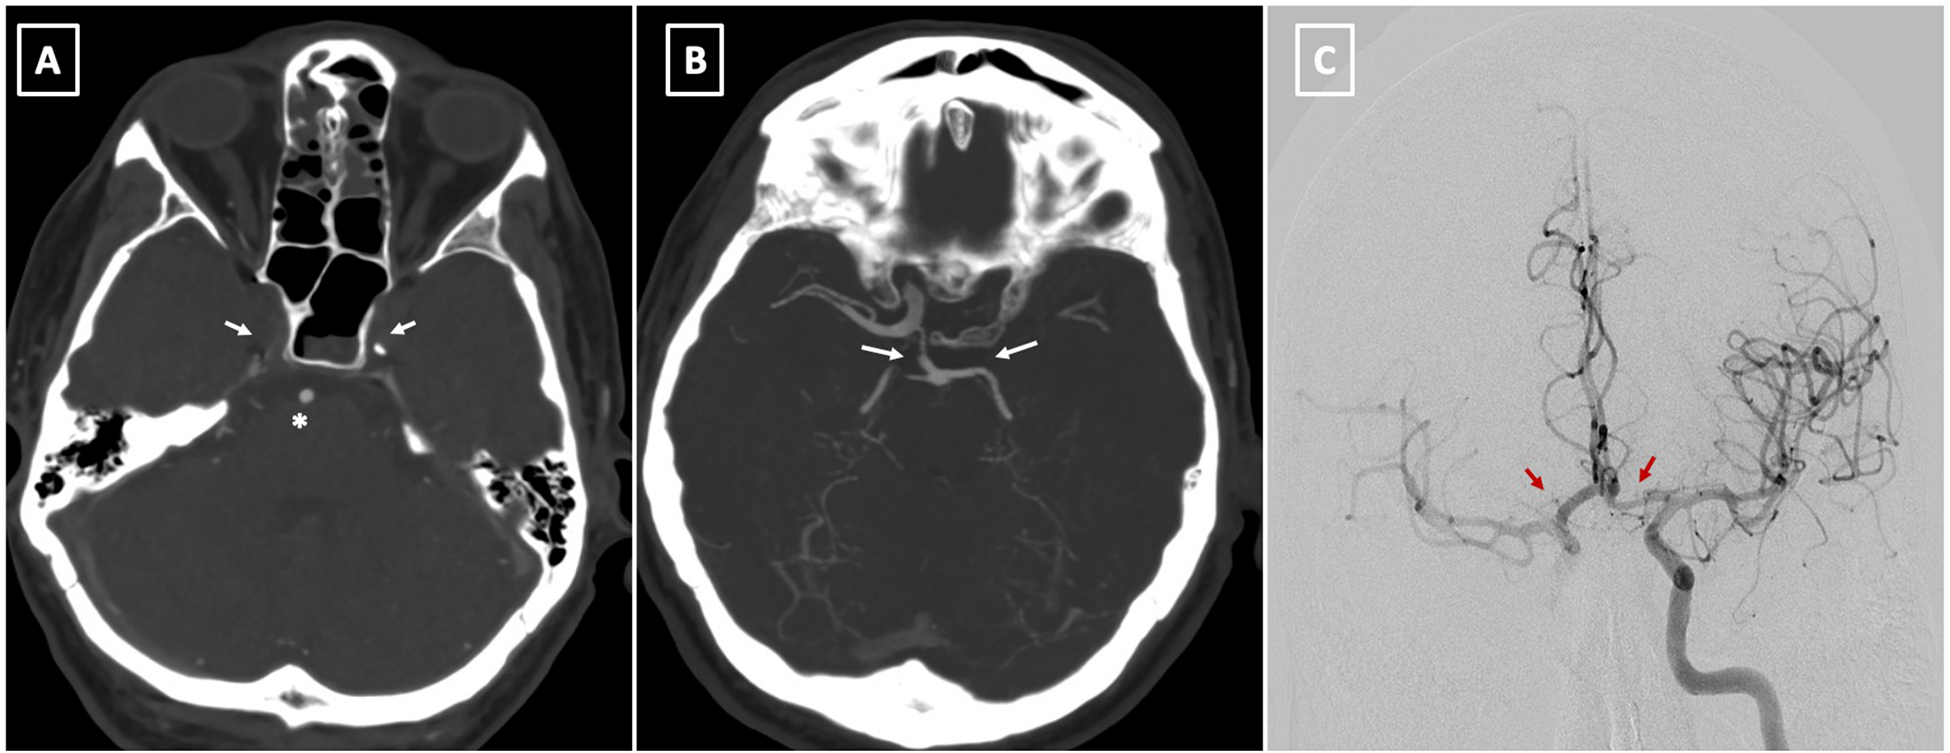

Postoperatively, the patient displayed right anisocoria and aphasia, with cerebral CT identifying bilateral occlusion of internal carotid arteries with a patent basilar artery (Figures 4A,B). Furthermore, the Maximal Intensity Projection (MIP) reconstruction highlights the distal filling of the right internal carotid artery through the patent right posterior communicating artery (Pcom). Notably, the left Pcom is absent, resulting in insufficient collateral flow to the left cerebral hemisphere. The Angiography revealed significant restriction of antegrade flow in the LCCA, markedly diminishing ipsilateral intracranial circulation. Endovascular stenting via the AMDS successfully recanalized the artery. Subsequent angiography post-stent deployment showcased restored patency in the LCCA and markedly improved circulation within the left carotid territory (Figures 4C, 5A,B).

Figure 4

(A) preoperative CT angiography at level of skull base demonstrates bilateral occlusion of internal carotid arteries (arrow) with a patent basilar artery (asterisk). (B) The Maximal Intensity Projection (MIP) reconstruction highlights the distal filling of the right internal carotid artery through the patent right posterior communicating artery (Pcom). Notably, the left Pcom is absent, resulting in insufficient collateral flow to the left cerebral hemisphere. (C) This image shows successful reperfusion of both cerebral hemispheres following the stent placement in the left common carotid artery (LCCA) (arrows).